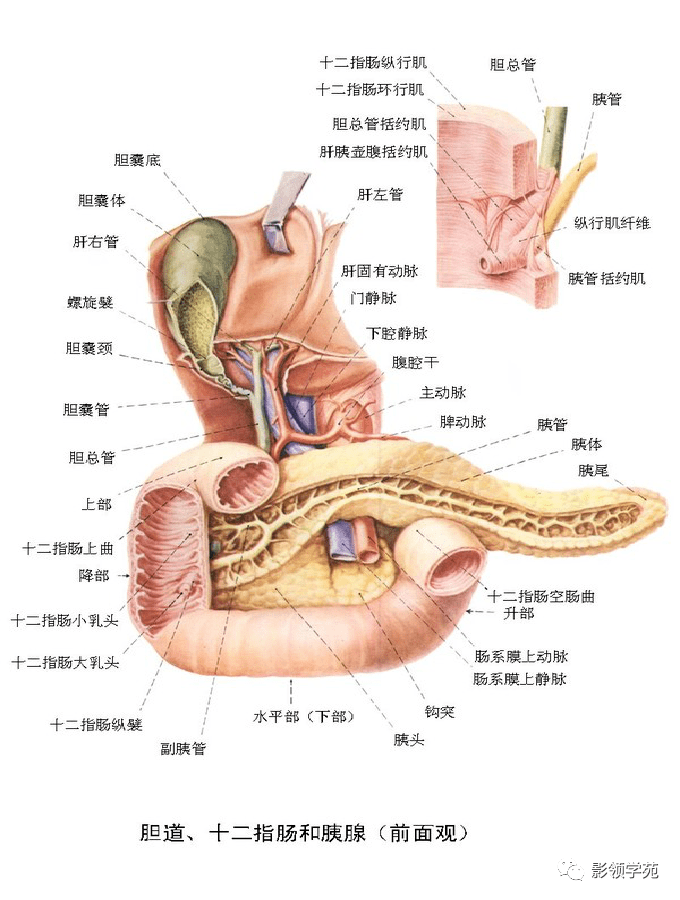

腹部动静脉

腹部动静脉